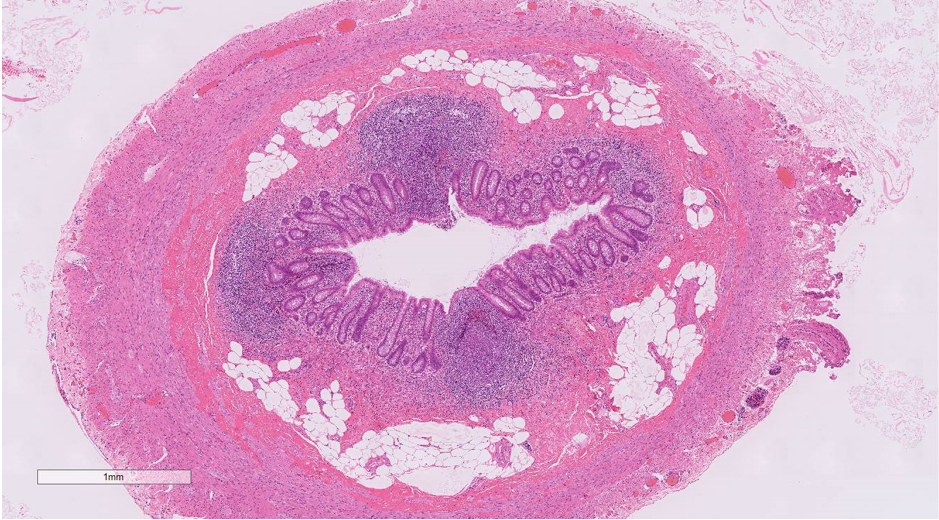

• HE ルーペ像